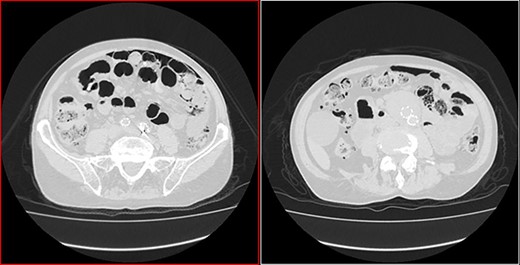

An 87-year-old male patient came to the radiology department to perform an abdominal computed tomography (CT) for follow-up of a bladder urothelial carcinoma. Upon CT evaluation, diffuse intestinal pneumatosis associated with pneumoperitoneum was identified on the exam (Fig. 1). The patient was called to return promptly to the hospital.

He arrived at the emergency department walking and with no clinical distress. He was complaining of hematuria for a month and worsening of chronic constipation in the last 2 days. Physical examination demonstrated discrete abdominal distention. Laboratory tests showed normal c-reactive protein (CRP), white blood cell count and lactate level. A new CT revealed no change in the previous findings: intestinal pneumatosis and pneumoperitoneum (Figs 2 and 3).

Transversal CT image in lung window showing pneumoperitoneum and pneumatosis intestinalis.

Coronal CT image in lung window showing pneumoperitoneum and ‘bubbles’ within the walls of small intestine and in the mesentery.